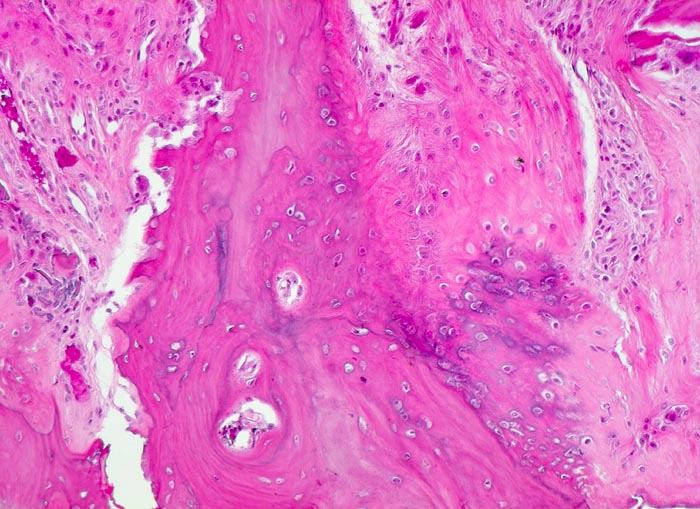

Makroskopisch ist die Nekrose im Anfangsstadium durch eine intensiv gelbe Verfärbung mit hämorrhagischem Randsaum charakterisiert. Häufig kommt es zur flächenhaften Ablösung des ansonsten intakten Gelenkknorpels (DD Arthrose!) zwischen subchondraler Knochenlamelle und angrenzender Spongiosa. In den Spätstadien sind die Nekrosezonen grau-gelb gefärbt und von körniger Konsistenz. Ein Teil der nekrotischen Spongiosabälkchen dient als Leitschiene für die Neubildung von Osteoid und mineralisierten Trabekeln, die an der Aussenseite angelagert werden. In der Nekrosezone kommt es zur Sequestrierung von Knochenbälkchen durch Frakturen. Die Markräume werden bindegewebig organisiert. In der Peripherie besteht initial ein hyperämischer Randsaum und im Verlauf kommt es zur Ausbildung einer metaplastischen Knorpel- und Knochenneubildung mit Randsklerose. Das Endstadium der Abräumreaktion untergegangener Knochenabschnitte stellt eine meist subchondral lokalisierte pseudozystische Umwandlung dar. Schliesslich kollabiert der Femurkopf und der Verlust der Gelenkkongruenz führt zu einer fortschreitenden sekundären Coxarthrose (> 3192)

• In der Nekrosezone osteoklastäre Resorption von avitalen sequestrierten Spongiosabälkchen.

• Ortsständiger Lamellenknochen wird als Leitschiene zur Fasernknochenneubildung benutzt.

• Fibrosiertes Mark mit einzelnen thrombosierten Arterien.